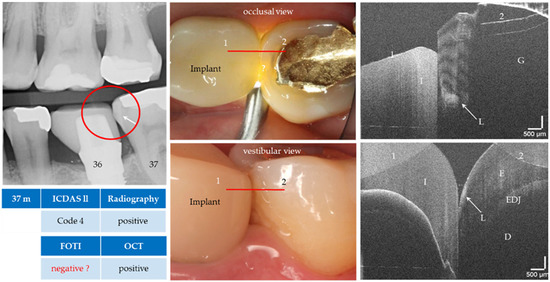

Caries, the world’s most common chronic disease, remains a major cause of invasive restorative dental treatment. To take advantage of the diagnostic potential of optical coherence tomography (OCT) in contemporary dental prevention and treatment, an intraorally applicable spectral-domain OCT probe has been developed [...] Read more.

Caries, the world’s most common chronic disease, remains a major cause of invasive restorative dental treatment. To take advantage of the diagnostic potential of optical coherence tomography (OCT) in contemporary dental prevention and treatment, an intraorally applicable spectral-domain OCT probe has been developed based on an OCT hand-held scanner equipped with a rigid 90°-optics endoscope. The probe was verified in vitro. In vivo, all tooth surfaces could be imaged with the OCT probe, except the vestibular surfaces of third molars and the proximal surface sections of molars within a "blind spot" at a distance greater than 2.5 mm from the tooth surface. Proximal surfaces of 64 posterior teeth of four volunteers were assessed by intraoral OCT, visual-tactile inspection, bitewing radiography and fiber-optic transillumination. The agreement in detecting healthy and carious surfaces varied greatly between OCT and established methods (18.2–94.7%), whereby the established methods could always be supplemented by OCT. Direct and indirect composite and ceramic restorations with inherent imperfections and failures of the tooth-restoration bond were imaged and qualitatively evaluated. The intraoral OCT probe proved to be a powerful technological approach for the non-invasive imaging of healthy and carious hard tooth tissues and gingiva as well as tooth-colored restorations. Full article